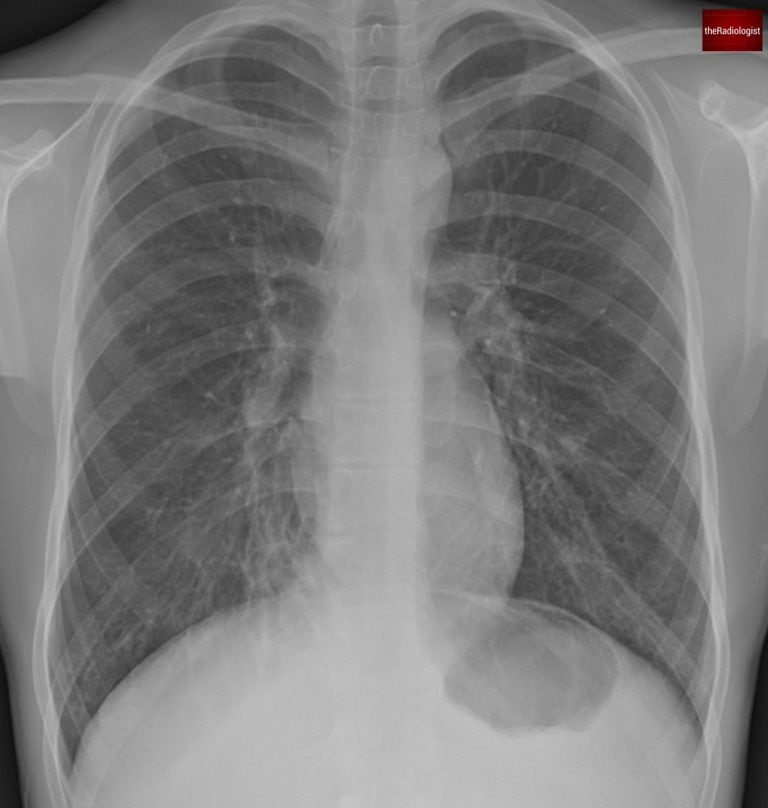

A man in his 20s attends his GP after struggling with recurrent chest infections. A chest X-ray is performed—do you see anything abnormal? This is a tricky one.

PA view of a chest X-Ray of a male in his 20s

When looking at a chest X-ray for someone in their 20s, you generally expect clear lungs with no abnormalities. So even subtle abnormalities in a patient of this age should not be taken lightly.

Let’s start by having a look at the right lung near the right heart border and compare with the same area within the left lower zone.

We can see the area of lung by the right heart border looks abnormal and if you look closely you can just make out a ‘ring shadow’. Ring shadows on a chest X-ray raise the possibility of bronchiectasis.